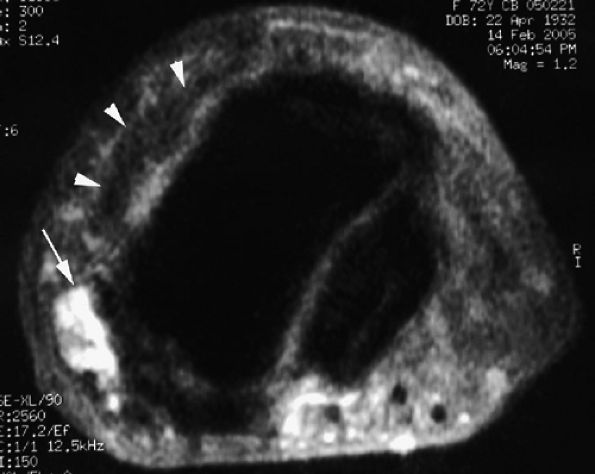

FIGURE 11.20 ● Acute injury of the radial collateral ligament (RCL) of the PIP joint of the fourth finger. Coronal (A) and axial (B) post-contrast fat-suppressed T1-weighted images displaying distal avulsion of the RCL with a proximal retraction (black arrows). The retinacular apparatus is displaced (arrowheads) with periligamentous edema. The ulnar collateral ligament is also identified (white arrows).